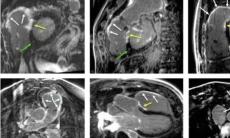

Cardio-RM-ul, cea mai complexa investigatie dedicata inimii si aplicatiile sale pentru pacientii din Romania

Principiul rezonantei magnetice a fost descris in 1946, dar debutul in imagistica dedicata aparatului cardiovascular a avut loc abia in anii 1970, cand a inceput sa fie aplicata pentru masurarea...